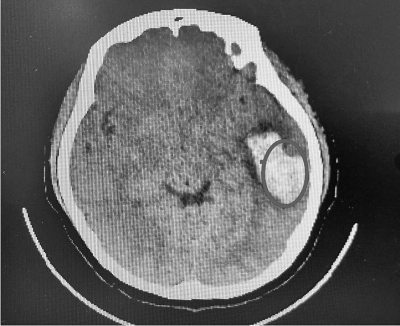

患者的脑部检查结果,圆圈处为出血区域。

当晚11点,欢欢被送到郑大一附院郑东院区。急诊医学部医生接诊后,检查发现女孩有脑出血发生,情况比较危急。“出血量比较大,有将近30毫升。如果发生在老年人身上,可能已经昏迷或偏瘫了。”副主任医师刘奇说,欢欢虽然年纪比较小,症状表现比较轻,但也不能大意。当时虽然欢欢没有带钱,但医院还是为她积极救治。